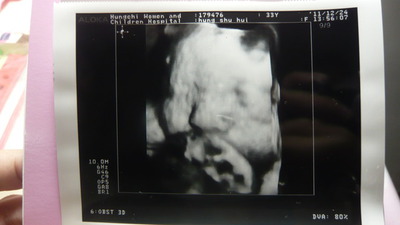

轉眼 懷著小土豆已經八個月啦我的體重:60.2公斤 小土豆:2075g妊娠糖尿低空飛過 喔耶!醫生用新的儀器 ... (詳全文)

七個半月  血糖OK!不用擔心有第二階段的四次抽血 從2D超音波裡  看見翩翩起舞的夢琪~(醫生說 ... (詳全文)